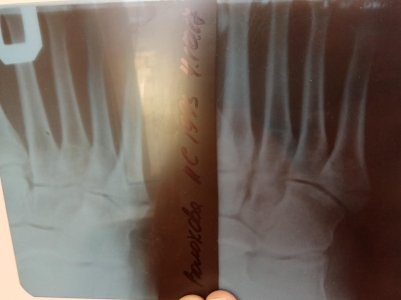

Перелом основания 5 плюсневой

24.09 сломала ногу. Сегодня 4.10 сказали динамики положительной нет, один врач говорит гипс на 4 недеди, другой твердит как минимум 6 плюс 2-4 недели реабилитация. По работе очень много приходиться ходить, понимаю, что вернусь не скоро, но не знаю какого врача слушать и хочу знать действительно ли нет вообще никакой динамики. Прикрепляю снимки: 24.09, 26.09 и 4.10 IMG_20171004_172546.jpg IMG_20171004_172630.jpg IMG_20171004_172701.jpg

24.09 сломала ногу. Сегодня 4.10 сказали динамики положительной нет, один врач говорит гипс на 4 недеди, другой твердит как минимум 6 плюс 2-4 недели реабилитация. По работе очень много приходиться ходить, понимаю, что вернусь не скоро, но не знаю какого врача слушать и хочу знать действительно ли нет вообще никакой динамики. Прикрепляю снимки: 24.09, 26.09 и 4.10Посмотреть вложение 14410 Посмотреть вложение 14411 Посмотреть вложение 14412

Здравствуйте! В ситуации с переломом ноги важно получить точную информацию о состоянии костей и динамике заживления. Обычно, если рентген показывает отсутствие положительной динамики, это может означать, что заживление идет медленнее, чем ожидалось. Время полного восстановления зависит от сложности перелома, возраста и общего состояния организма. Лучше всего обратиться к травматологу или ортопеду, который наблюдает за вашим лечением, чтобы получить конкретные рекомендации и понять реальную ситуацию.